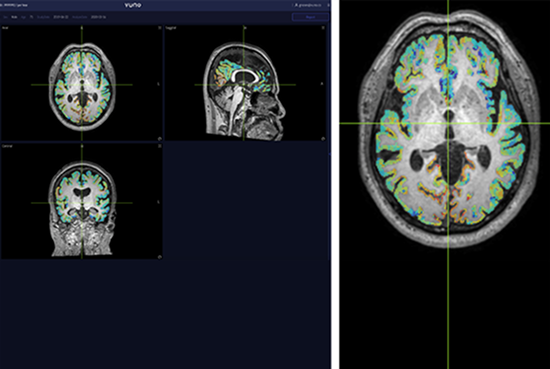

The software assists in the diagnosis of neurodegenerative diseases such as Alzheimer's disease based on percentile scores and volume information for one hundred brain areas.

• Provides volumetric data on 100 different regions through brain parcellation.

• Provides information of brain atrophy through the analyzed volume data.

• Provides information of normative percentile, the relative score compared to the normal average

• Visualizes the cortical thickness (0-7mm) through a Color Map on the MRI image.